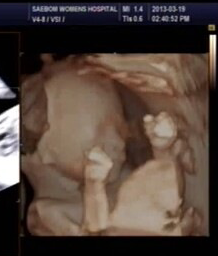

자작도아니고 합성도 아니고 미국아이초음파사진도 아니예요.

그날찍은 다른 초음파사진 더 올릴게요.

날짜랑시간까지다찍혀있어요...

이모가 태어날 조카 초음파사진이 너무신기하고 이뻐서 올린사진이예요ㅎ

동생이 지금 임신중인데...

이번에검진갔다 초음파사진을 찍었는데 혼자보기 아깝고 넘 신기해서요ㅋ

일케완벽하게쁘이를ㅎㅎ 신기하지않나요?? ㅎ

(왼쪽 뇌가 저렇게 나오는것은 뇌가 덜 생긴게 아니라 초음파를 찍을때 약간 선명하게 나오는정도를 오른쪽 부분으로 맞춰서 그런겁니다. 다시 왼쪽 부분 쪽으로 맞추면 왼쪽 부분이 완성되서 나오구요 저때 되면 손가락 발가락 뇌 뼈 두개골형태 하며 있을꺼 다 있습니다)